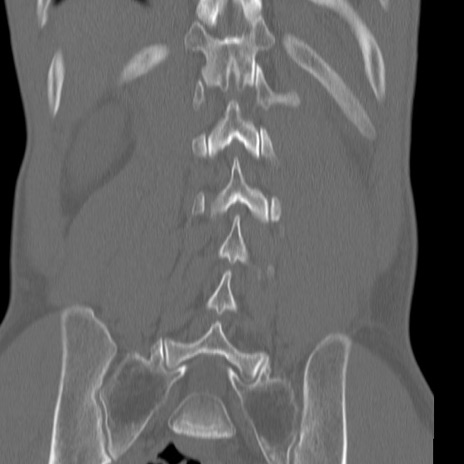

症例3 腰椎CT(冠状断像)

腰椎CT

矢状断像